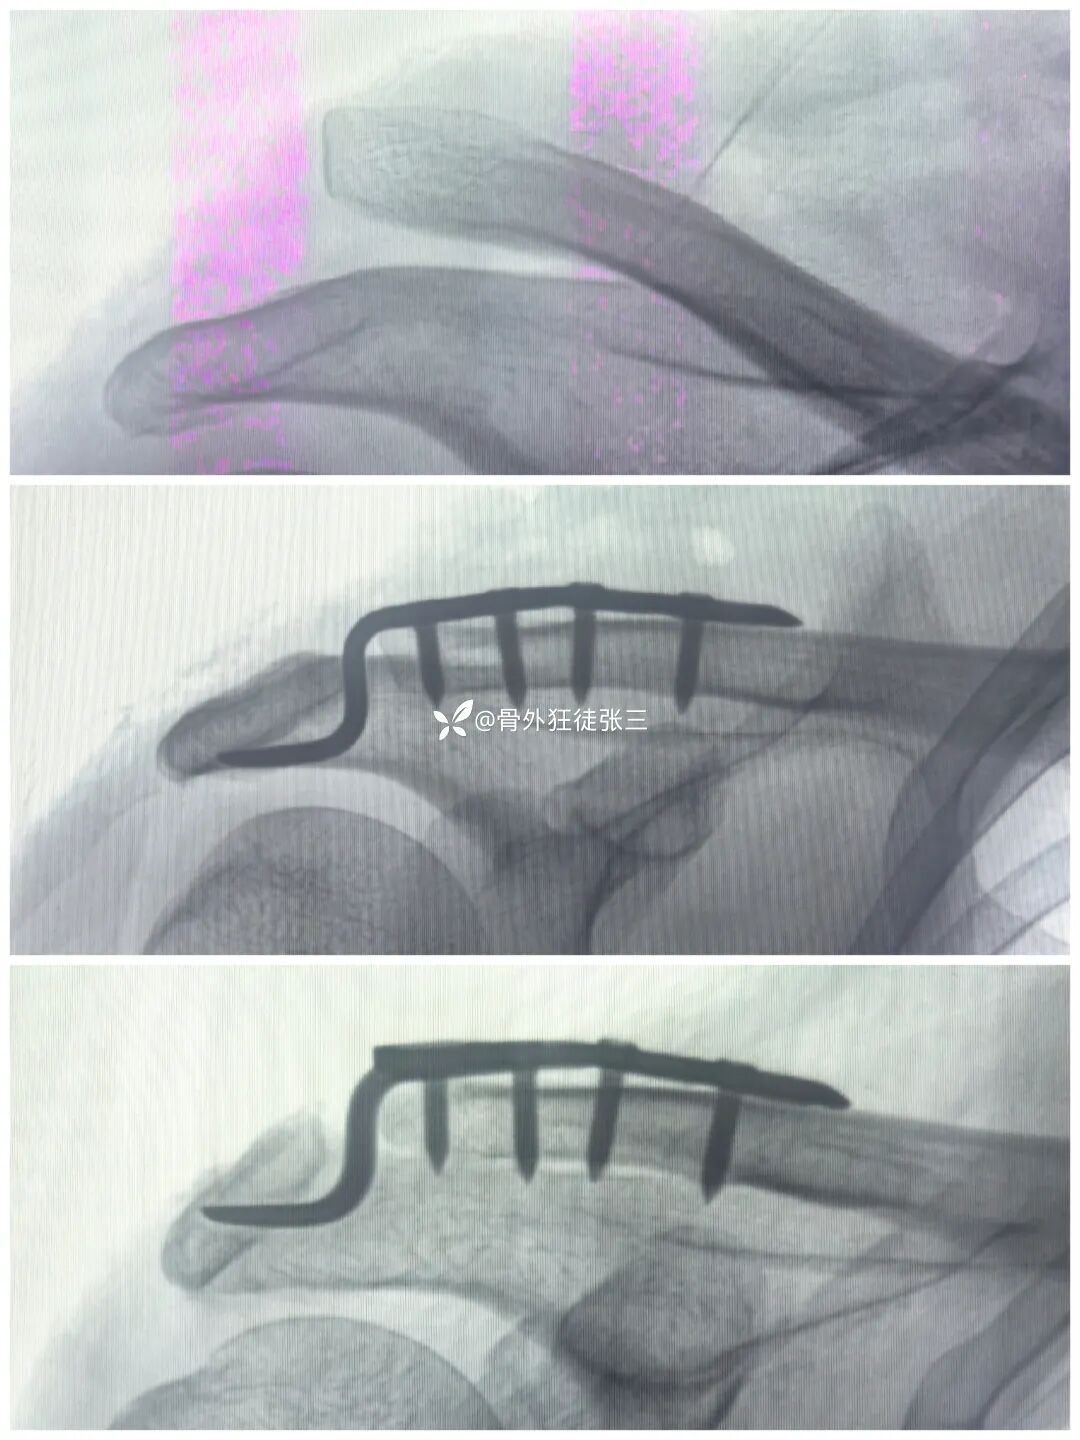

病例三:

取出后,查体肩锁关节稳定

复查关节间隙正常

术中麻醉下顺便给患者肩关节做一个手法松解

术后第2天,今天,查房患者诉

“肩膀(关节)前所未有的轻松”